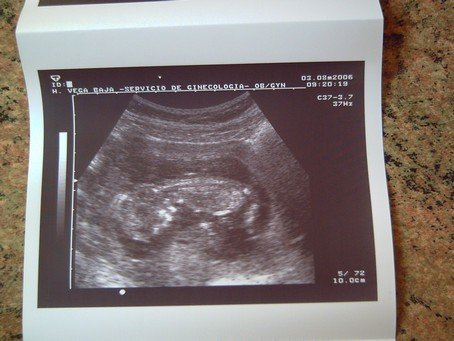

Én meg ígértem 18 hetes UH képet: :D

azért szeretem az UHos képeket mert az anyukán kívül senki nem lát benne semmit :lol: De olyan mint egy jó játék, lehet találgatni mi is van a képen :) Tontica felső képén egy geninc "gyöngysorát", Takidoén egy koponya ívét látom. Mit nyertem? :lol:

Az enyémen valóban látszik a koponyája, jobb oldalon,mellette látszik a pocija+még a combcsontja is bal oldalon,az alsó lábszárát eldugta valahova :D